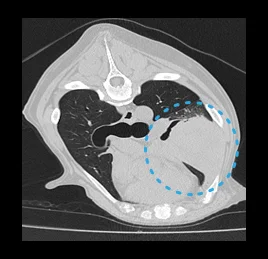

• 흉부 질환

폐 종양, 폐 염전, 원발 종양의 폐 전이 평가, 심장 종양,

종격동 종양, 흉벽 종양

• 폐 염전

• 폐 종양